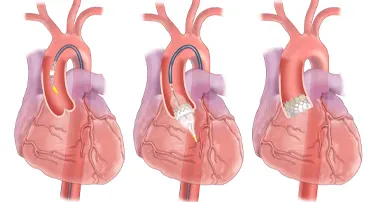

Innovative Heart Valve Solutions That Avoid Open-Heart Surgery

For decades, open-heart surgery was the sole method for repairing or replacing a defective heart valve. Although effective, the old method is marked by giant incisions, extended recovery periods, and jeopardy to elderly or high-risk patients.

TAVI Vs. Open-Heart Surgery: Which Is The Right Choice For You?

For heart valve replacement, patients usually have two primary choices: Transcatheter Aortic Valve Implantation (TAVI) and open-heart surgery. Both involve replacing a faulty aortic valve, but they are very different in approach, recovery period, and applicability to various patient populations. Knowing the main differences, advantages, disadvantages, and success rates can assist you in making an informed choice.

Who Is The Ideal Candidate For TAVI? Understanding Eligibility & Benefits

Transcatheter Aortic Valve Implantation (TAVI) has revolutionized the treatment of severe aortic stenosis, especially for patients who are high-risk candidates for traditional open-heart surgery. This minimally invasive procedure offers a lifeline to many, but determining who stands to benefit the most is crucial.

Modern Cardiac Care: The Role of TAVR in Structural Heart Disease Treatment

Nature is just amazing. Look at the amazing things. Just look around, or better yet, look within yourself. Your heart, for example, is a true marvel, working tirelessly, 24/7, never taking even a nap.